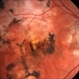

- serpiginous choroiditis

- Imaging device

- Fundus camera

- Serpiginous choroiditis, right eye #1. Advanced pigmented scar formation ( fovea involved).